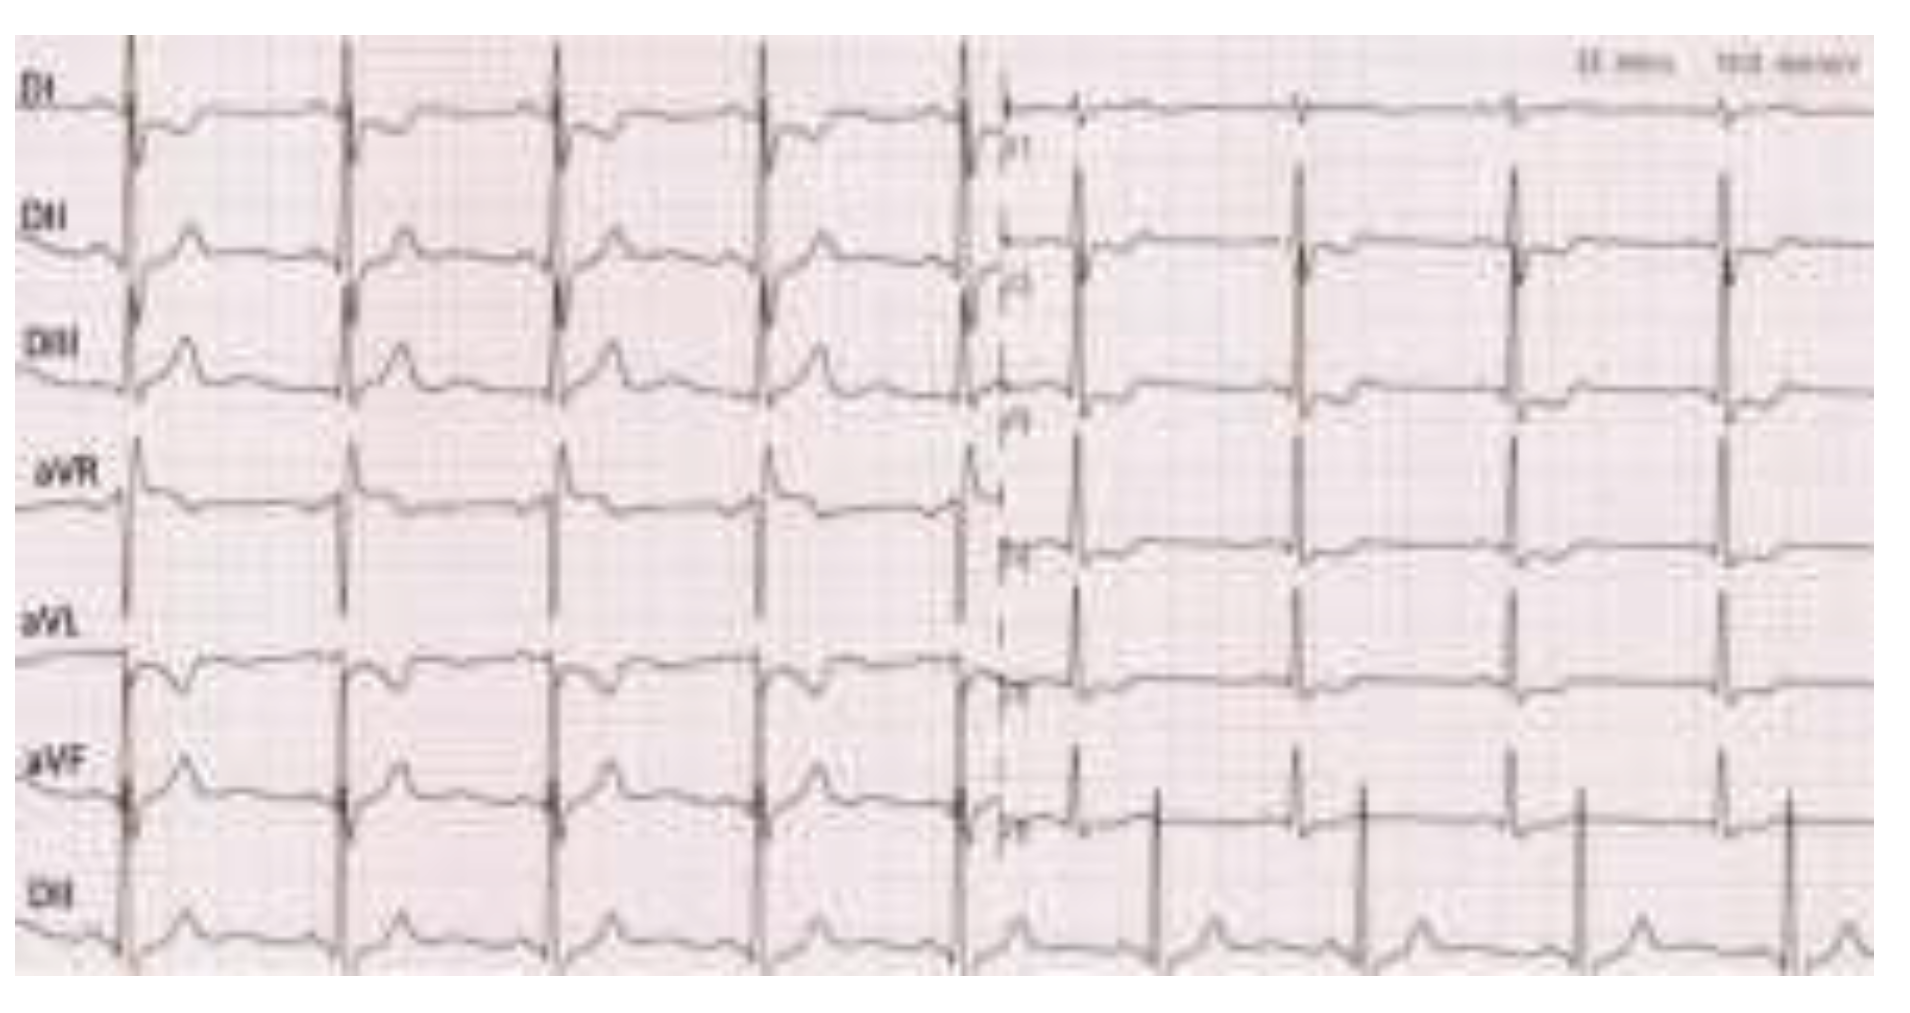

- Non-ST segment elevation myocardial infarction.

- Incomplete right bundle branch block.